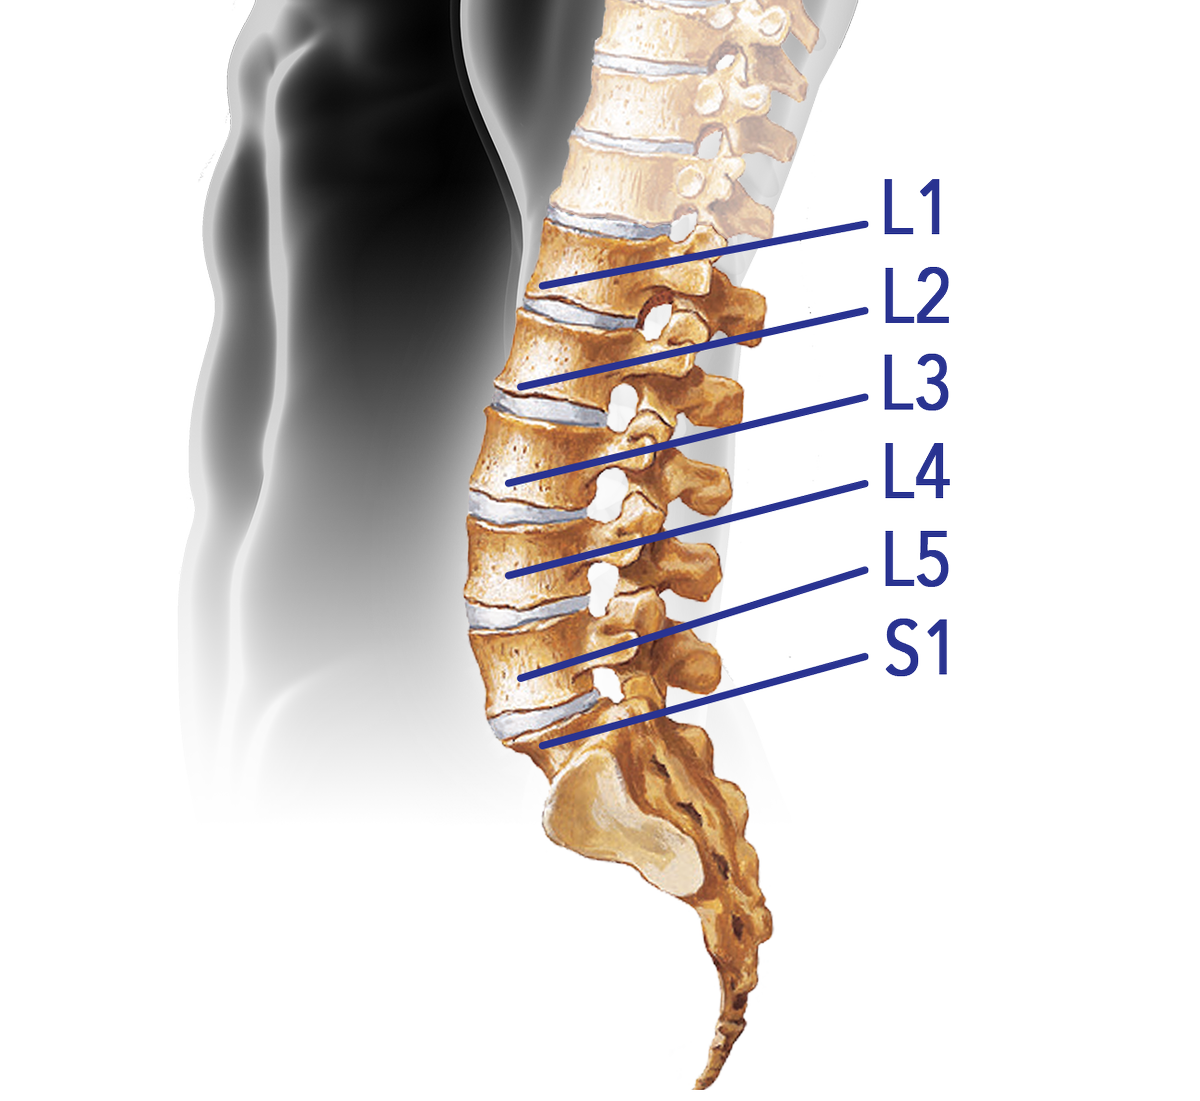

Lumbar Spine – TrialExhibits Inc.

The lumbar spine with the segments representing L1, L2 … L5 vertebras …

Spine Diagram L4 L5 S1 | My XXX Hot Girl

Anatomy of the Lumbar Spine – TrialExhibits Inc.

Learn all about lumbar spine anatomy from a world-renowned Spine Expert …

Endoscopic Spine Surgery: An Alternative to Lumbar Spinal Fusion …

spine l2 l3 l4 l5